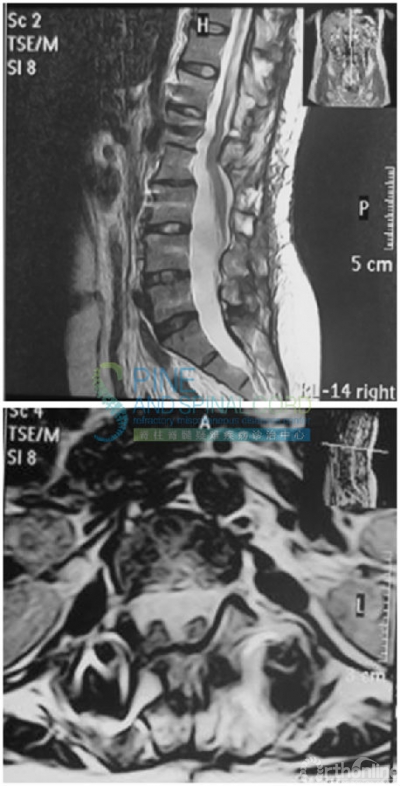

病例三 脊髓栓系综合征伴腰椎间盘突出

患者男,45岁,因右下肢疼痛无力2年,加重1年入院。

便秘10年,尿急尿频、漏尿1年

体检:左下肢肌力正常、右下肢肌力4级,腓肠肌萎缩,左下肢腱反射活跃、右下肢腱反射减退,病理征未引出